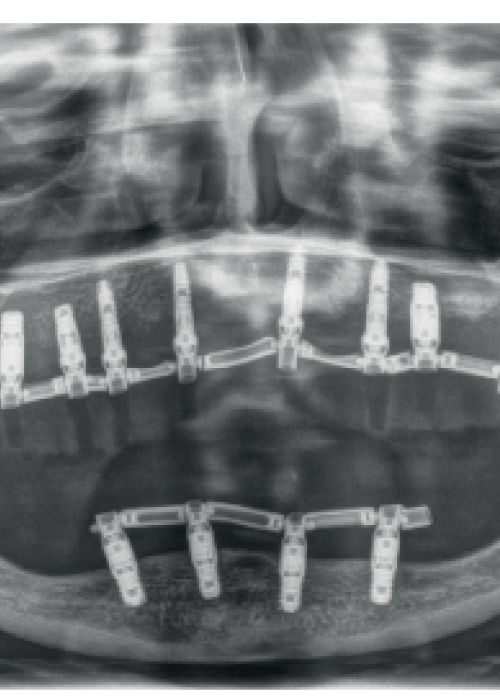

Explantación de implante mal posicionado en sector estético y regeneración posterior con injerto en bloque

Implantes de 4,5 y 5,5 mm longitud insertados de forma directa en elevación crestal con hueso autólogo unido al Endoret-PRGF en alturas óseas residuales de 2-3 mm: estudio retrospectivo